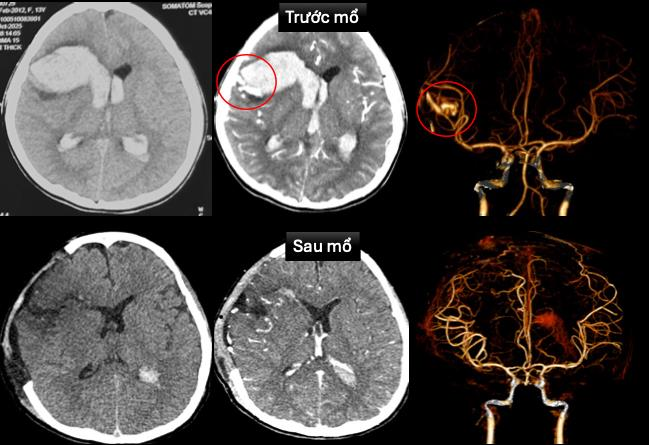

Ngày 6/11, TS.BS Trần Minh Huy, Khoa Ngoại Thần kinh, Bệnh viện Nhi đồng 1, cho biết bệnh nhi được tuyến trước chuyển đến trong tình trạng hôn mê sâu, phải thở máy qua nội khí quản, nhịp tim chậm, huyết áp thấp. Siêu âm tim, chụp cắt lớp vi tính sọ não ghi nhận vỡ dị dạng động tĩnh mạch trán phải, gây xuất huyết não, kèm sốc tim, rối loạn nhịp,...

Các bác sĩ nhiều chuyên khoa hội chẩn để xử trí cấp cứu. Bác sĩ tim mạch can thiệp đặt máy tạo nhịp tạm thời. Bác sĩ ngoại thần kinh phẫu thuật cấp cứu mở sọ giải áp, vi phẫu cắt dị dạng mạch máu não, lấy máu tụ trong nhu nhô não và não thất.

Sau phẫu thuật, bé được điều trị hồi sức tích cực, thông khí cơ học, dùng thuốc vận mạch và chống phù não. Hiện, bệnh nhi đã tỉnh táo, chỉ còn yếu nhẹ chân phải, tim mạch ổn định. Hình ảnh chụp não sau mổ cho thấy không còn dị dạng mạch, chức năng tim cải thiện rõ.